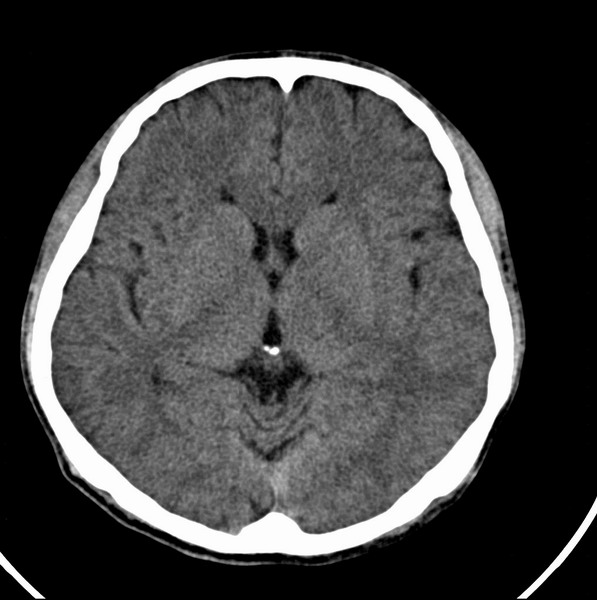

男、29

突发痴呆,失语,记忆减退,反应迟钝二十小时。

右侧额叶低密度影,边界清晰,无占位效应,符合:额叶皮质脑软化灶。

左额叶也有类圆形低密度影,同右侧低密度灶近颅底一层同层,病灶周脑实质密度似稍高,成环状,这个没有问题么?

考虑右侧额叶脑软化灶;建议必要时行mri检查排除其他。

考虑皮质软化灶。不考虑胶质瘤,是因为胶质瘤一般发生于白质内。